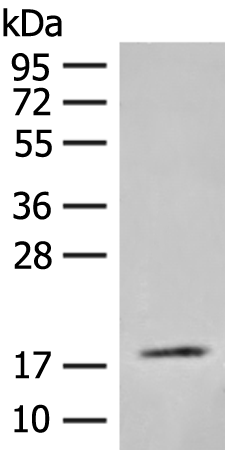

分类: 科研抗体货号: P43575别名: fetal hemoglobin; HBGA; HBGR; HBG-T2; HSGGL1; PRO2979; TNCY; HBG-T1应用: WB,IHC反应种属: Human